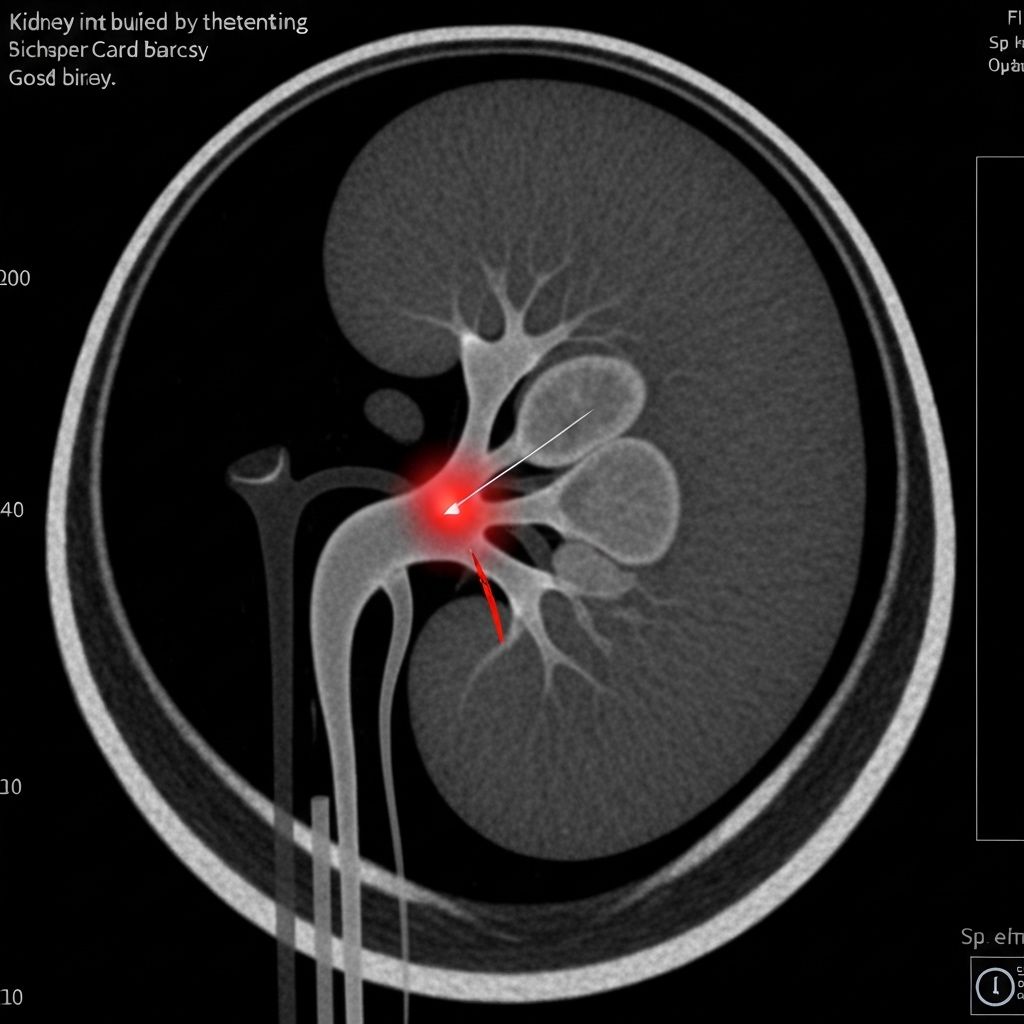

Lesión renal sospechosa

Procedimiento

Biopsia percutánea

Resultado

Diagnóstico histopatológico claro con mínima complicación

Recuperación

Paciente estable en 24 horas